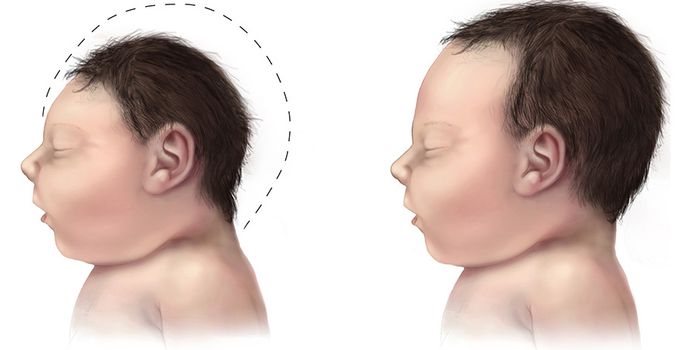

AUG 26, 2016Cell & Molecular BiologyMicrocephaly is a rare developmental defect that causes an infant’s head to be smaller than normal at birth. While ...

MAR 11, 2016Clinical & Molecular DXHealth officials have long suspected a correlation between the Zika virus and microcephaly, but they didn’t know t ...